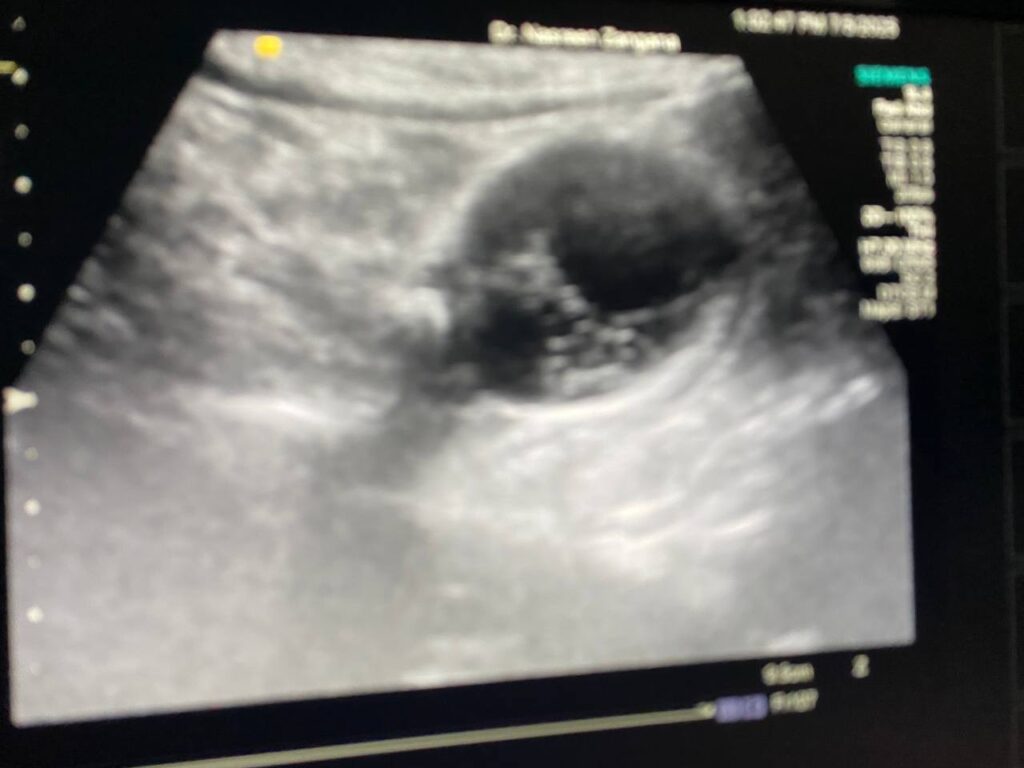

U/S : Gall bladder : distended , contain stone 9mm , full with heterogenous fluid , contain multiple honeycomb septations , also associated with pericholecystic edema 3.5mm , picture mostly of acute on chronic cholecystitis , please for further study normal common bile duct